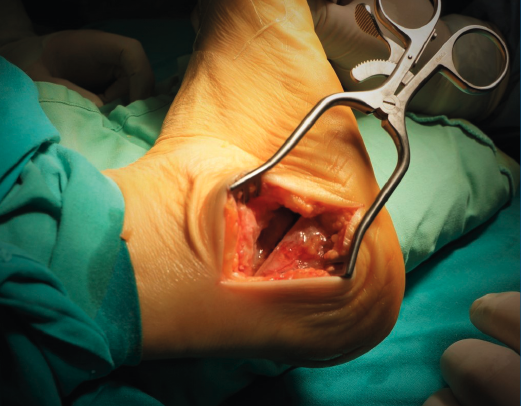

Introducción y objetivos: la enfermedad de Müller-Weiss (EMW) es una patología causada por la displasia del navicular que, en muchos casos, está mal o infradiagnosticada. Se presenta como un “pie plano-varo paradójico” y una artropatía talonavicular. En este trabajo pretendemos explicar nuestra experiencia con una cirugía de preservación articular –osteotomía “supervalguizante” de calcáneo aislada (de tipo Dwyer con desplazamiento lateral)– en nuestra primera serie de pacientes a los que no se realizó una artrodesis.

Conclusiones: la EMW produce un pie plano paradójico. La corrección quirúrgica del varo subtalar permite una mejoría clínica y radiológica notable. La osteotomía “supervalguizante” es una técnica sencilla y se ha constituido en nuestra técnica de elección, independientemente del estadio radiológico. La artrodesis de la columna medial ha quedado como técnica de rescate para fracasos de la cirugía de preservación articular.

Introduction and objectives: Müller-Weiss disease (MWD), a tarsal navicular dysplasia, is often misdiagnosed or underdiagnosed. Clinical presentation as a paradoxical “flatfoot varus” combines with arthritic talonavicular changes. In the present study we show our experience with a joint-preserving surgical treatment –isolated “super-lateral-slide osteotomy”– in the first series of patients in which a tarsal arthrodesis was not performed.

Conclusion: MWD presents with a paradoxical flatfoot varus. Surgical correction of hindfoot varus allows for a mechanical change that produces clinical and radiological improvement. An isolated “super-lateral-slide osteotomy” is an easy technique to achieve varus correction regardless the radiographic stage of the disease and has become our surgical procedure of choice. Medial column arthrodesis is left as a salvage procedure for those cases that do not improve with the osteotomy.